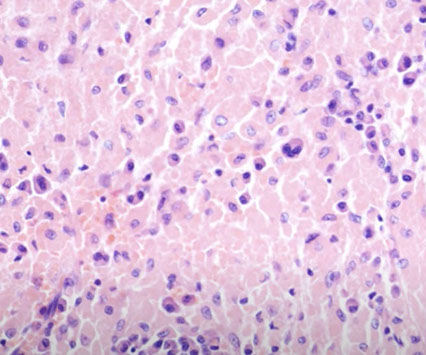

Toxoplasma Lympadenitis

Infection with Toxoplasma gondii. One of the MC parasitic dz's of humans; typically in the posterior cervical LNs of young women, which are firm and moderately enlarged

Micro: the triad -

1) reactive follicular hyperplasia c lots o mits and phagocytosis of nuclear debris;

2) small granulomas made of pink epithelioid histiocytes in the paracortex that encroach and involve the GCs

- should NOT have well-formed granulomas (which you may see with sarcoidosis), multinucleated giant cells, or necrosis

3) distention of sinuses by monocytoid B cells

- not common to see find T gondii organisms

Toxoplasma lymphadenitis. Has lots of reactive follicles, intact capsule with patent subcapsular sinus getting closer to hilum. Increased follicles almost back to back, but have well-preserved and well-defined mantle zones and preservation of the interfollicular areas. There are lots of pinkish cells, which are epithelioid histiocytes which surround and encroach upon involved follicles [3]

Epithelioid histiocytes in toxoplasma infection [3]

Monocytoid B-cells in Toxoplasma lymphadenitis [7]

Classic triad of monocytoid cells, enlarged follicles with reactive germinal centers, and epithelioid histiocytes encroaching germinal centers in Toxoplasma [7]